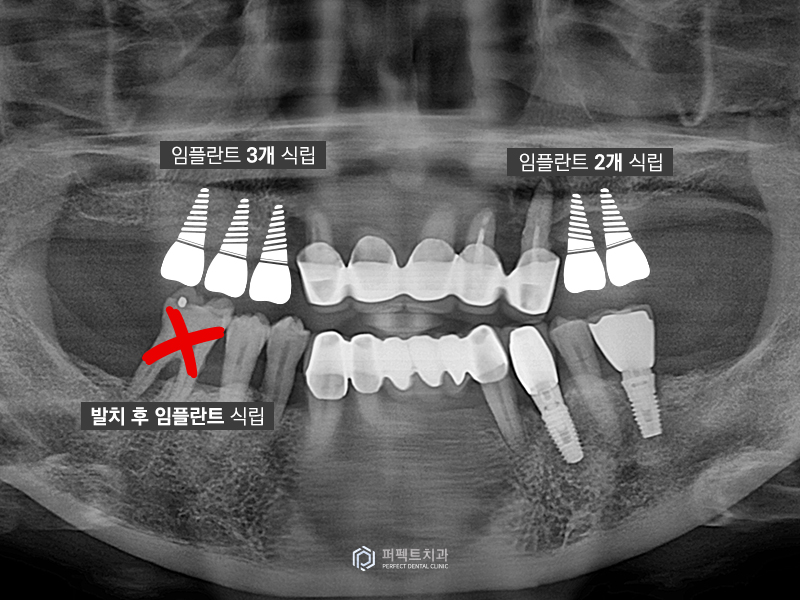

그래서 환자분이 원하시는 대로 방향을 설정하여 계획에 맞게 수술을 하였고 오른쪽 3개, 왼쪽 2개의 임플란트를 심어 밑에 치아까지 저작을 할 수 있도록 간단하게 하는 방법으로 계획을 세웠습니다.

아래 표시된 치아도 붕 떠있는 치아인데 이 치아도 발치한 후 임플란트를 식립하여 총 6개의 임플란트를 식립한 케이스입니다. 또한 환자분께서는 네비게이션 임플란트를 원하셔서 본 원에서 자체적으로 네비게이션 가이드를 제작하여 수술하였습니다.